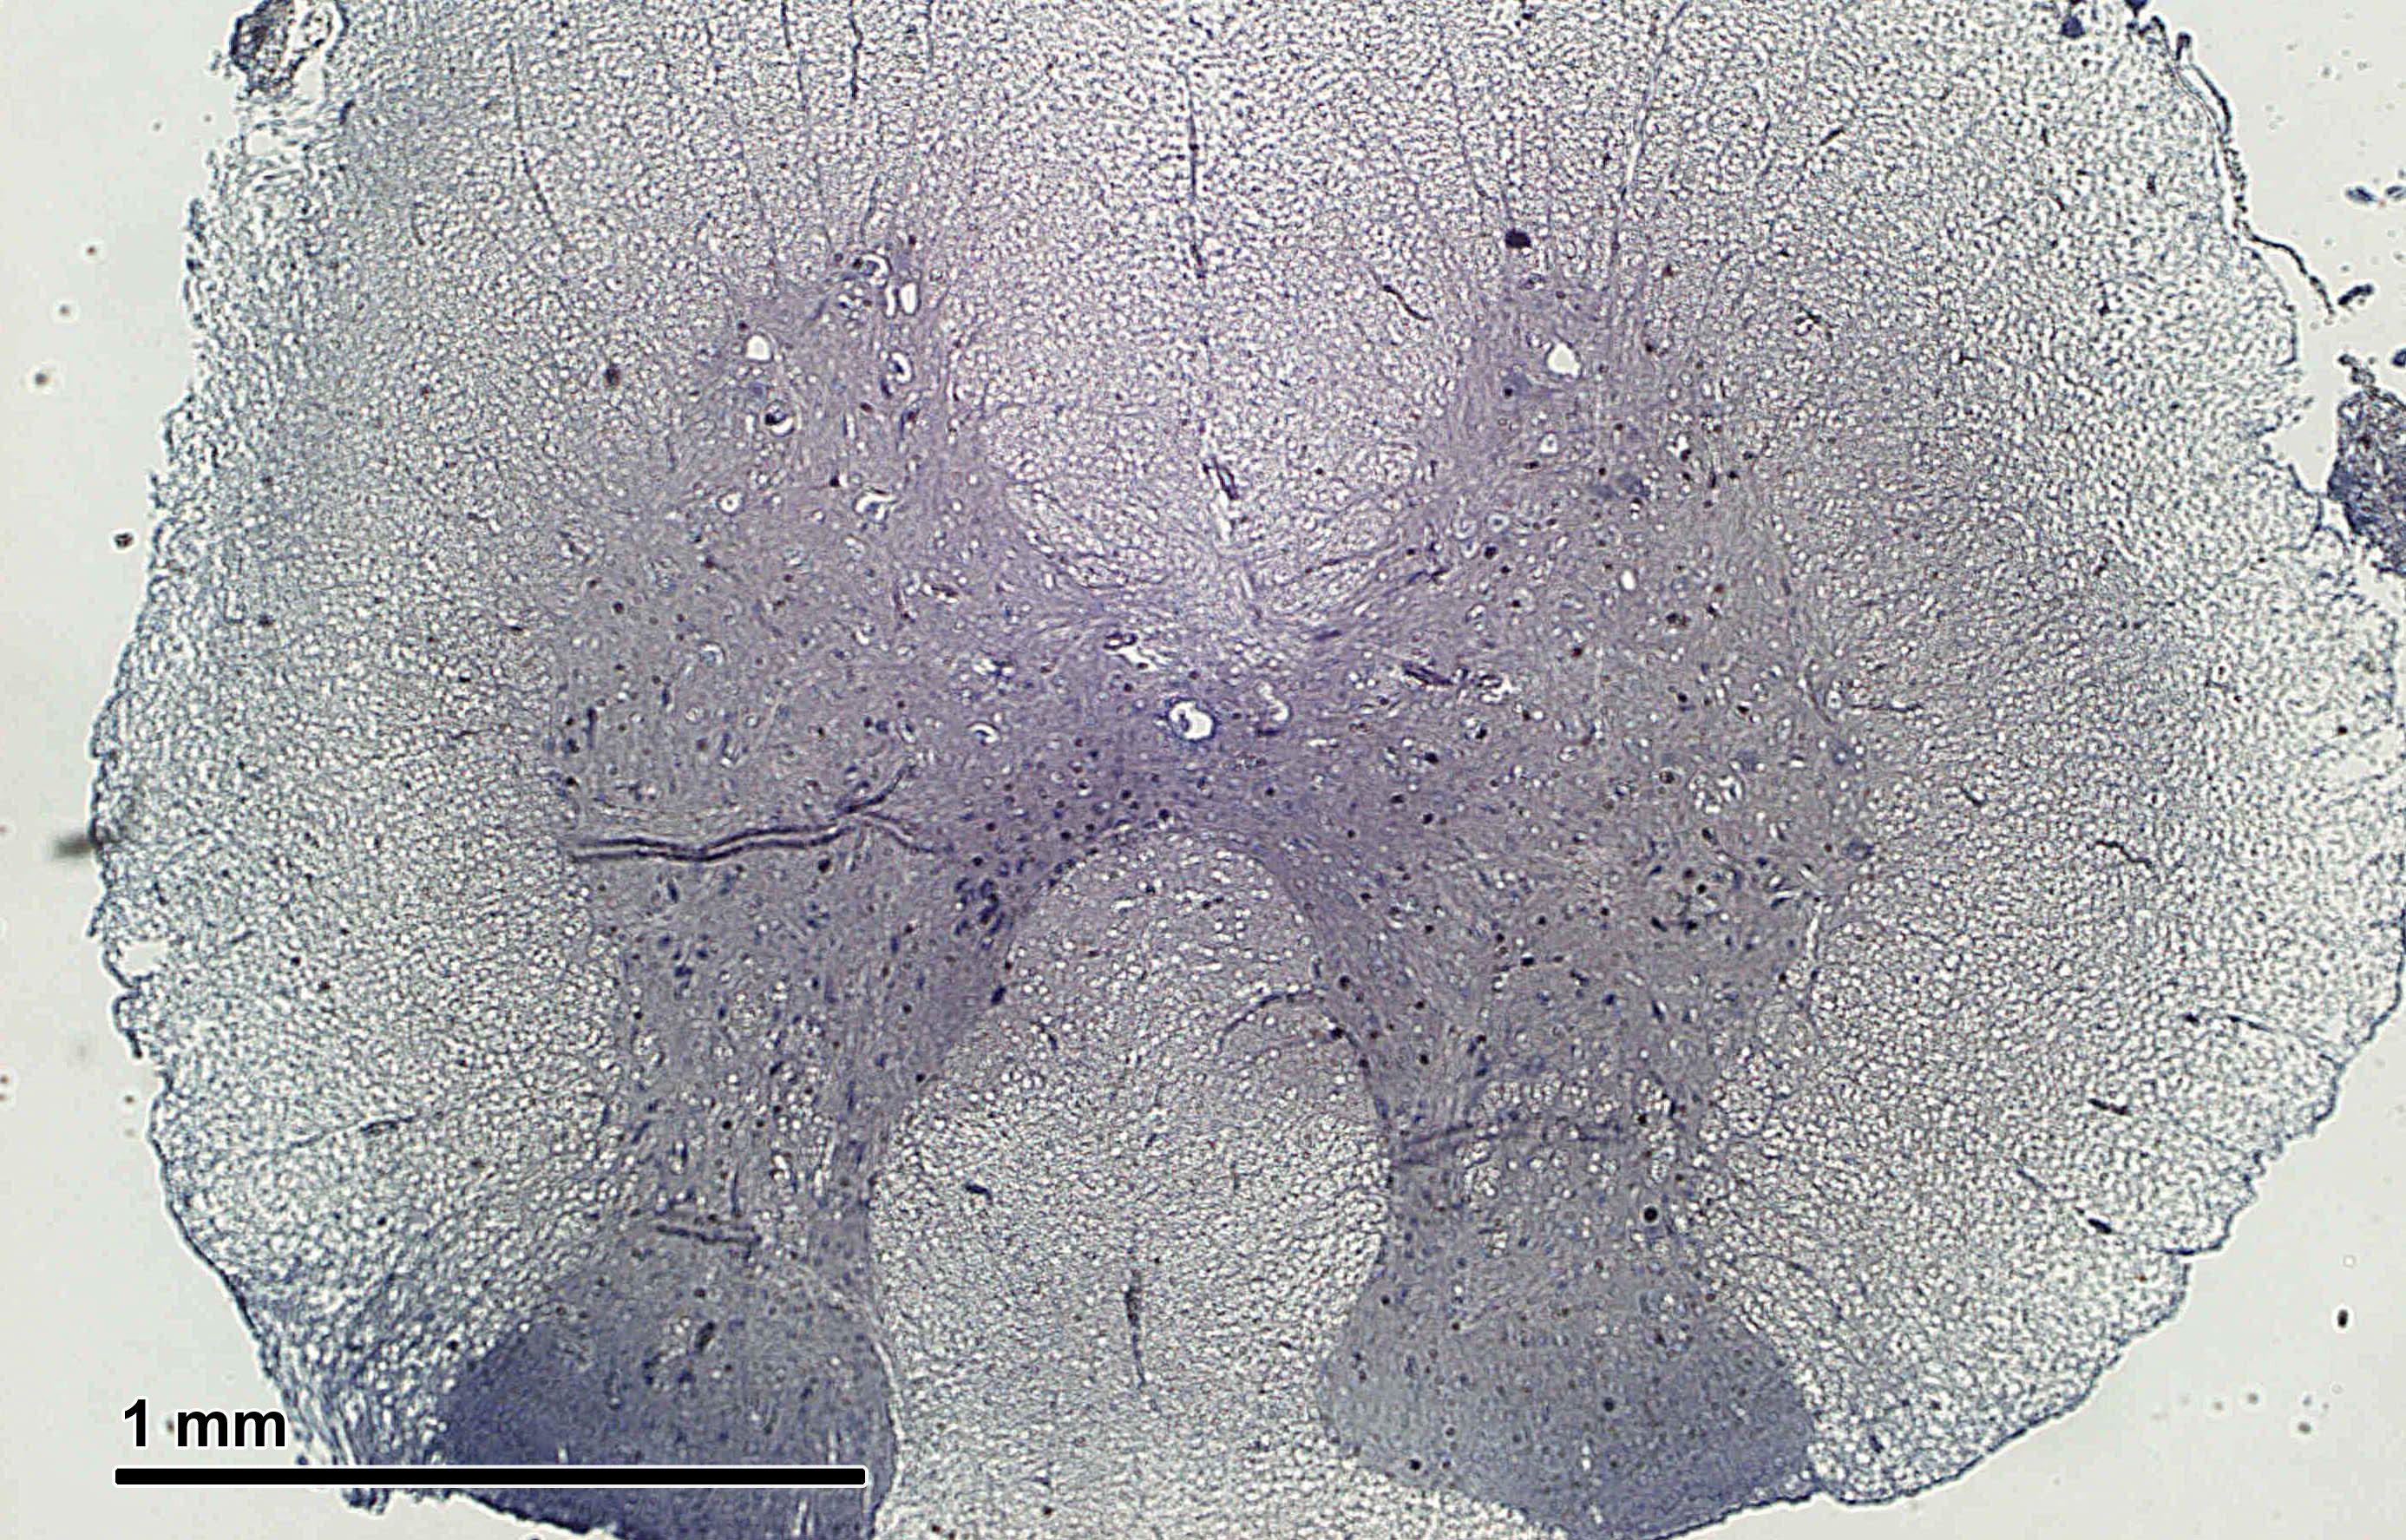

신경조직은 신경세포체와 축삭의 분포에 따라 회색질과 백색질로 구분된다.

중추신경계에서 신경세포체가 모여 있는 부분은 비교적 짙게 보여 회색질이라고 부르고, 축삭이 모여 있는 부분은 미엘린 때문에 희게 보이므로 백색질이라고 부른다. 회색질에는 신경세포체와 가지돌기가 있으므로 시냅스도 대부분 이곳에서 이루어진다. 축삭, 가지돌기 및 신경아교세포 돌기들이 어지럽게 얽혀 신경그물(neuropil)을 이룬다. 백색질에는 축삭, 신경아교세포, 혈관이 있으며 신경세포체는 존재하지 않는다. 백색질의 축삭 가운데 출발 지점과 도착 지점이 서로 비슷해 구조적, 기능적으로 밀접하게 연관되어 있는 것들을 묶어 신경로라고 일컫는다.[22]

회색질과 백색질의 배열 양상은 부위에 따라 다르게 나타난다. 척수에서는 회색질이 안쪽, 백색질이 바깥쪽에 위치한다. 대뇌와 소뇌에서도 중심부에 바닥핵(기저핵)이라는 회색질 덩어리들이 존재하고 백색질이 그 주변을 둘러싸고 있지만, 척수와 달리 가장 표면 부위에 추가적으로 회색질 층이 있어서 대뇌겉질 및 소뇌겉질을 형성한다. 뇌줄기에서는 회색질과 백색질을 구분하기 어렵다.[22]

3. 1. 회색질과 백색질

회색질은 신경세포체, 가지돌기, 무수축삭, 신경아교세포 등이 모여 있는 영역으로, 주로 정보 처리를 담당한다. 백색질은 유수축삭, 신경아교세포 등이 모여 있는 영역으로, 신경세포 간의 정보 전달 통로 역할을 한다. 뇌와 척수에서 회색질과 백색질의 배열 양상이 다르다.[22]척수에서는 회색질이 안쪽에, 백색질이 바깥쪽에 위치한다. 대뇌와 소뇌에서도 중심부에 바닥핵(기저핵)이라는 회색질 덩어리들이 존재하고 백색질이 그 주변을 둘러싸고 있지만, 척수와 달리 가장 표면 부위에 추가적으로 회색질 층이 있어서 대뇌겉질 및 소뇌겉질을 형성한다. 뇌줄기에서는 회색질과 백색질을 구분하기 어렵다.[22]